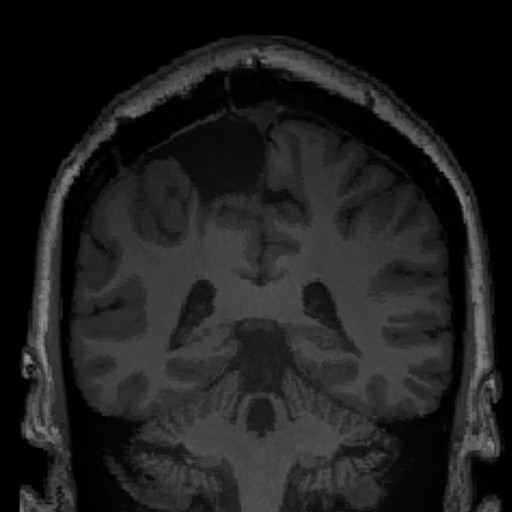

Processing. Multi-modal MRI standardization and quality control form the open-source foundation available for research use

Analysis. Whole-brain morphometric mapping reveals deviation patterns across cortical and subcortical structures